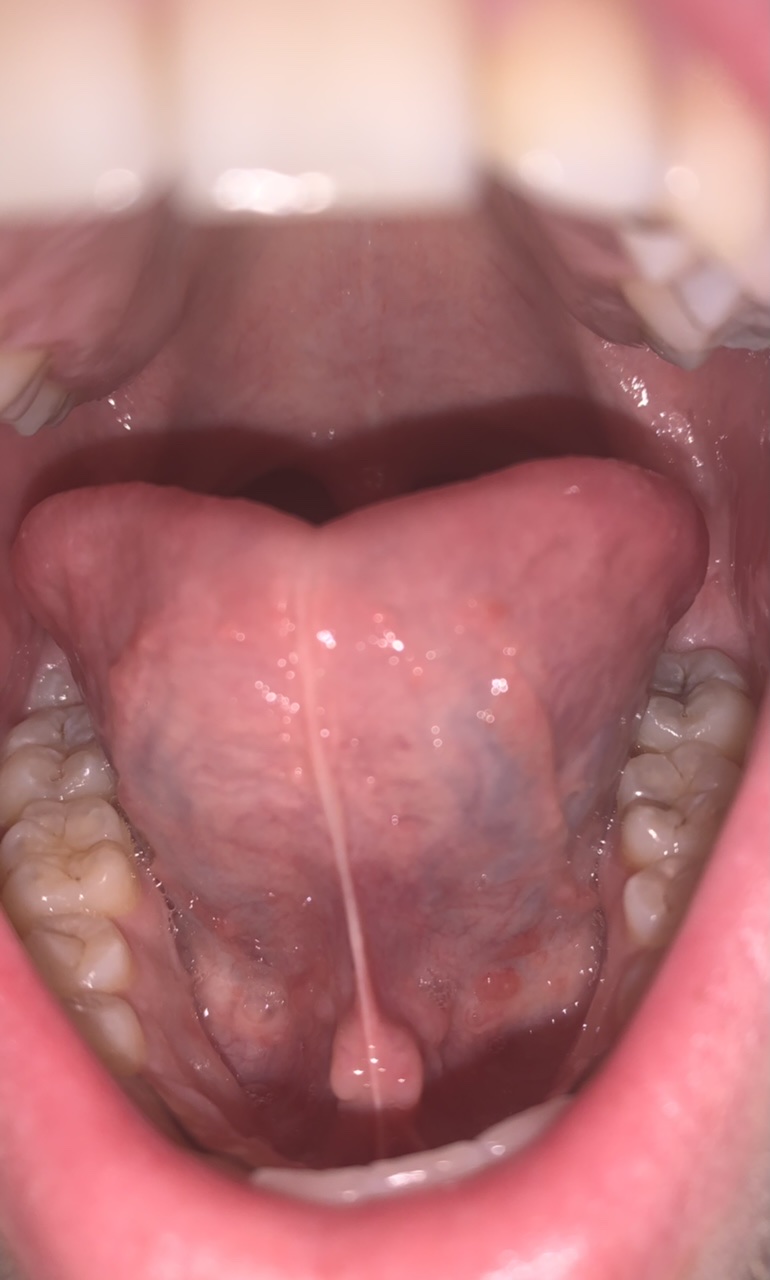

Hoi, ik ben een jongen van 18. Tijdens het controleren van mijn doorkomende verstandskiezen zag ik ineens onrust onder mijn tong. Het is wat rood en er zijn bultjes te zien.

Ik heb er geen last van, maar de bultjes (zie afbeelding) zijn wel te voelen als ik hier met mijn vinger overheen ga en het lijkt of er op sommige een ‘kopje’ bloed op zit.

Mijn vraag is: Klopt het dat de ruimte onder mijn tong onrustig is? Hoe komt het? En is dit iets om zorgen over te maken?

Zoals te zien, zijn er nog wel rode blaasjes en de twee ‘draden’/‘lijnen’ die via mijn tong omhoog lopen. Over Het laatst genoemde weet ik niet of het normaal is of niet, maar het viel mij op. Wat denkt u ervan?